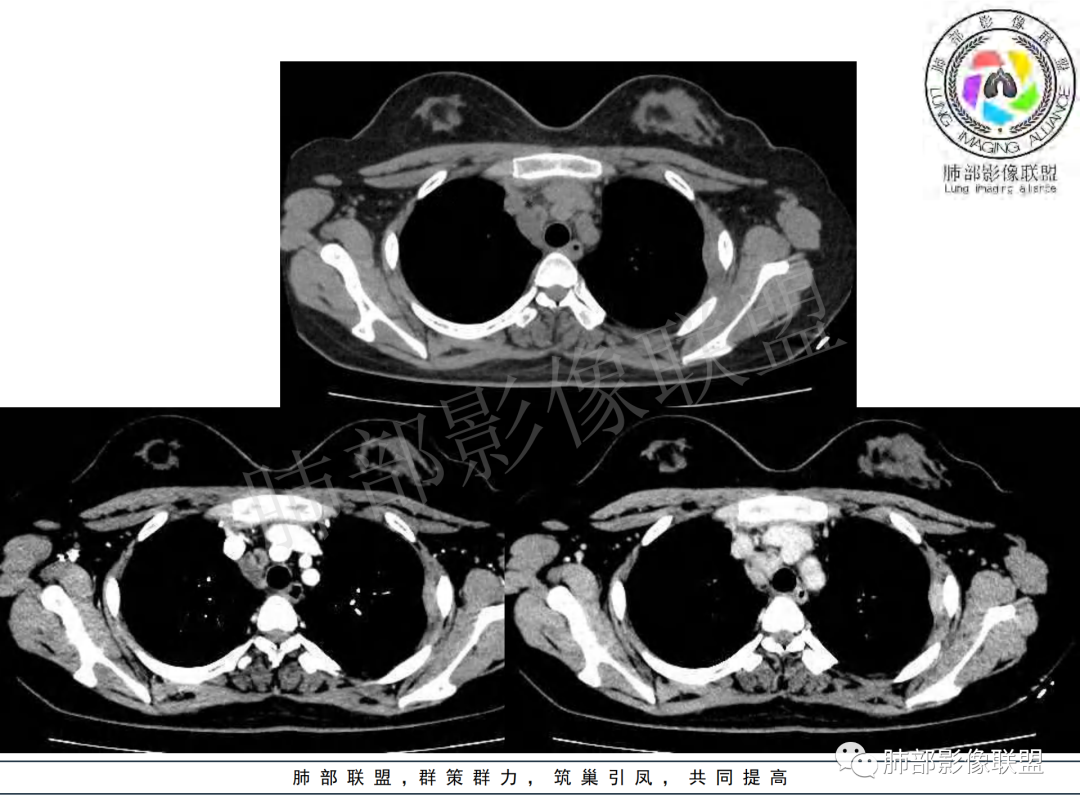

纵隔多组及右侧肺门多发肿大淋巴结,部分融合,不均匀强化,内见斑片状坏死区及环状强化,后者坏死边界尚清晰,肺门区肿大淋巴结与肺组织边界不清,年轻女性,8个月病史,发热首发症状,考虑淋巴结核并向肺内侵及(破溃?),鉴别淋巴瘤

女,20,病程长达8月,发热、胸痛、右侧胸腔积液病史。胸部CT:右肺门旁不规则肿块影,右中间支气管腔内结节,纵隔多发淋巴结肿大;强化不均匀,灶性坏死灶,环形强化;右侧少量胸腔积液并局部肉芽肿样突起。年轻女性,长病程,多部位,考虑慢性炎症,结核?鉴别肿瘤。

年轻女性,慢性病程,发热、胸痛。右肺门旁不规则肿块影,纵隔多发淋巴结肿大;强化不均匀,环形强化;右侧少量胸腔积液;首先考虑结核,鉴别肿瘤,结节病。

慢性病程,前纵隔右肺门旁多发淋巴结肿大;强化不均匀,环形强化;右侧少量胸腔积液;考虑结核,鉴别结节病。

青年女性,发热、胸痛、右侧胸腔积液病史,病程8个月。曾多次抗炎后均有好转。CT:右肺门旁肿块影,双侧胸膜结节,纵隔多发淋巴结肿大,边缘模糊;增强渐进性明显强化,纵膈淋巴结较彻底坏死灶,边缘环形强化。考虑结核,鉴别恶性肿瘤。

女性,20岁。高热、畏寒。右肺上叶近肺门区不规则肿块,周围斑点、片小结节影伴肿大淋巴结,肿块包绕并突入右主支气管腔内,增强后肿块不均匀强化,淋巴结环形强化中心低密度,考虑结核。

本例患者,年轻女性,慢性病程,多次抗感染治疗效果不佳,实验室检查示白细胞及中性粒细胞不高,不支持普通细菌感染,虽然肺泡灌洗液X-Pert检测阴性,结合患者胸部CT结核感染亦不能排除,胸部CT主要表现为右侧肺门及纵隔淋巴结肿大,仔细观察不难发现右中间支气管内新生物凸向管腔内,增强扫描,右肺门(10R)及纵隔淋巴结(2R,4R)明显不均匀强化,内部呈不规则低密度无强化区,被周边高强化区包绕(环形强化)的特点,首先应当想到纵隔淋巴结结核诊断。淋巴结分布亦不符合肺部恶性肿瘤迁徙途径。